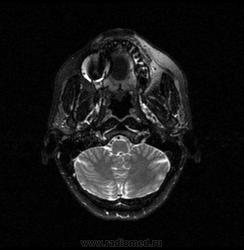

06.06.2011 МРТ - головы и шеи.

Пацентка 36 лет, с жалобами на припухлось в околоушной области справа.

В глубокой доле  правой околоушной железы  на фоне неизмененной паренхимы зона  гетерогенного по Т2, гипоинтенсивного по Т1  с единичными гиперинтенсивными включениями.При контрастировании- накопление контраста диффузное неоднородное и по периферии.Рискну предположить злокачественное образование ( аденокарцинома) с низкой степенью злокачественности( есть капсула, экспансивный рост).Сильно не расстреливайте.

Проблема в том, что перед челюстно-лицевым хирургом стоит распространенность любого объемного процесса, в данном случае все упирается в возмможную травму лицевого нерва и конечно же с дальнейшим его парезом, а ведь женщина  еще молодая. Образование имеет тонкостенную оболочку, по структуре неоднородно, с наличием кальцината, при этом МР-сигнал от окружающих анатомических структур(как костных так и мышечных) не изменен, т.е. об инфильтративном росте речи не идет, в какой то степени доброкачественное. В конкретном случае лицевой нерв с ретромандибулярной веной просто несколько оттеснен.

По гистологии аденома околоушной слюнной железы, но после удаления пока сохраняется парез лицевой мускулатуры, возможно временный.